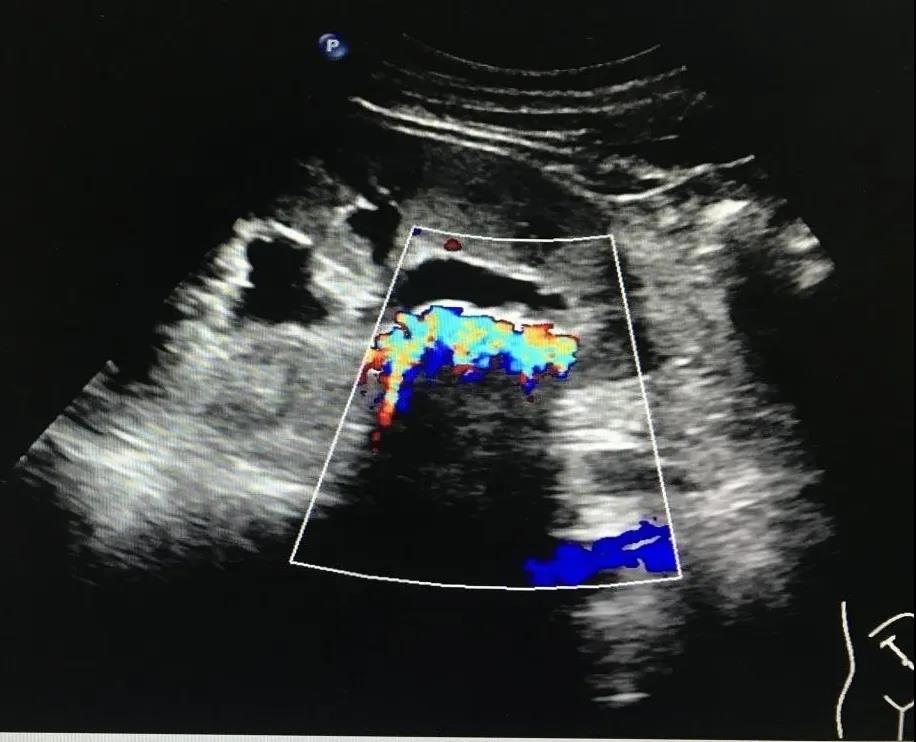

圖2:箭頭所示結(jié)石,彩色多普勒后方伴閃爍偽像

2.中等結(jié)石:高強(qiáng)團(tuán)狀回聲一般呈新月?tīng)?,后方聲影明顯。CDFI特征性顯示“閃爍”偽像,有助于結(jié)石的識(shí)別(見(jiàn)圖2)。